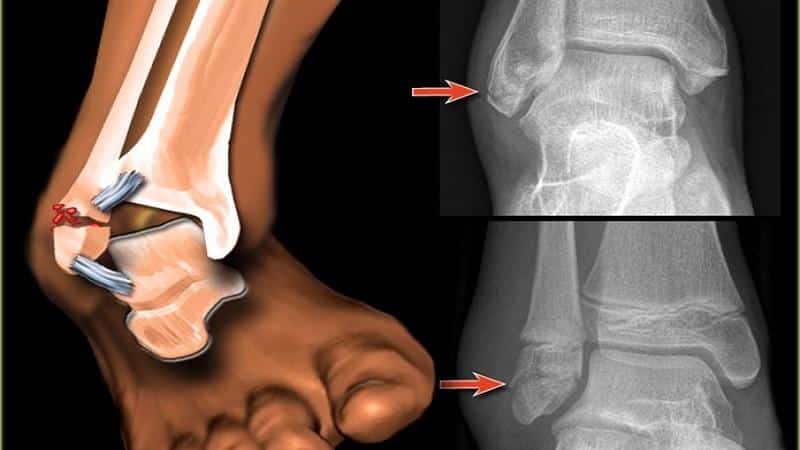

Предварительный диагноз ставят на основании симптомов переломов лодыжек, к которым относятся боль, деформация стопы в области голеностопного сустава и изменение цвета кожи. Для подтверждения диагноза понадобится клиническое обследование, включающее пальпацию проксимального большеберцово-малоберцового сочленения, а также костей голени по всей длине, связочного аппарата голеностопного сустава.

Для определения стратегии лечения назначается рентгенография голеностопного сустава в двух стандартных проекциях (боковой и переднезадней). На снимках определяются линии изломов, направление и степень смещения отломков, вид подвывиха и степень расхождения берцовых костей. В некоторых случаях назначают компьютерную томографию голеностопного сустава. Если необходимо оценить состояние мягких тканей, проводят магнитно-резонансную томографию голеностопного сустава.